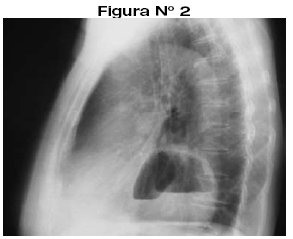

<body><![CDATA[<p align="justify"><font face="Verdana" size="2">Se trata de un paciente de 50 años de edad, de sexo femenino, que acude al servicio de diagnóstico por imágenes para exámenes radiológicos de rodillas, columna dorsolumbar y test de Farrel; observándose incidentalmente en la radiografía de columna imágenes de anormalidad y luego se indica radiografía de tórax PA y Lat. donde se observa imagen radioopaca con nivel hidroareo (<a href="#f12">Figura N&deg; 1,2</a>). </font></p>     <p align="justify"><a name="f12"></a></p>     <p align="center"><img src="/img/revistas/rmcmlp/v18n2/a06_figura_01.jpg" width="252" height="257"></p>     <p align="center">&nbsp;</p>     <p align="center"><img src="/img/revistas/rmcmlp/v18n2/a06_figura_02.jpg" width="293" height="239"></p>     <p align="justify"><font face="Verdana" size="2">Se complementa el mismo con un examen contrastado de esófago y estómago, observándose que el cardias, el estómago y parte del duodeno se hallan por encima del hiato o sea en la cavidad torácica. (<a href="#f3">Figura N&deg; 3</a>).</font></p>     <p align="justify"><a name="f3"></a></p>     <p align="center"><img src="/img/revistas/rmcmlp/v18n2/a06_figura_03.jpg" width="301" height="266"></p>     <p align="center">&nbsp;</p>     <p align="justify"><font face="Verdana" size="3"><b>DISCUSIÓN</b></font></p>     ]]></body>